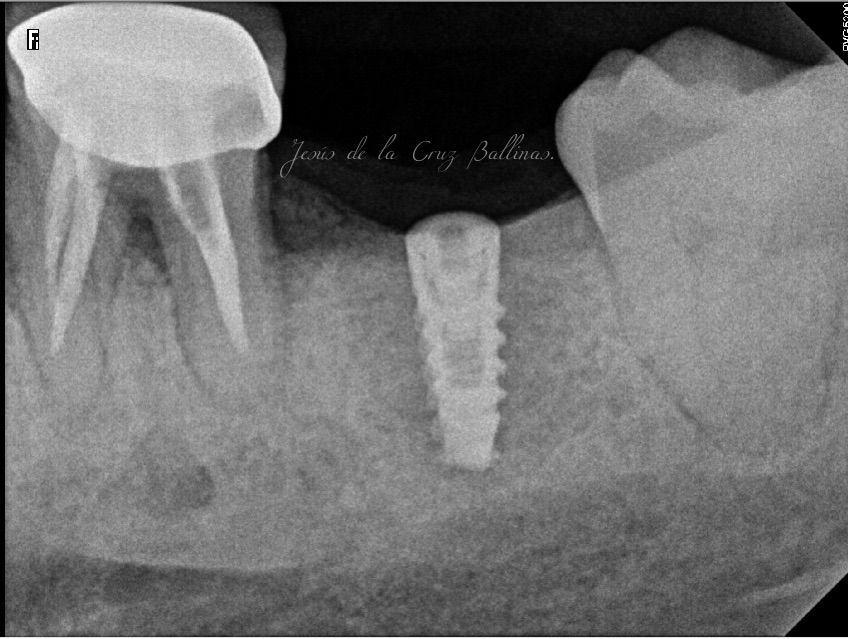

Especialista en Implantología Oral quirúrgica y protesica, cédula de especialidad: 12411844

La especialidad en Implantología Oral se enfoca en sustituir órganos dentarios perdidos por implantes dentales mediante una fase quirúrgica y una fase protesica y de esta manera devolver la función, estetica y confort dental del paciente.